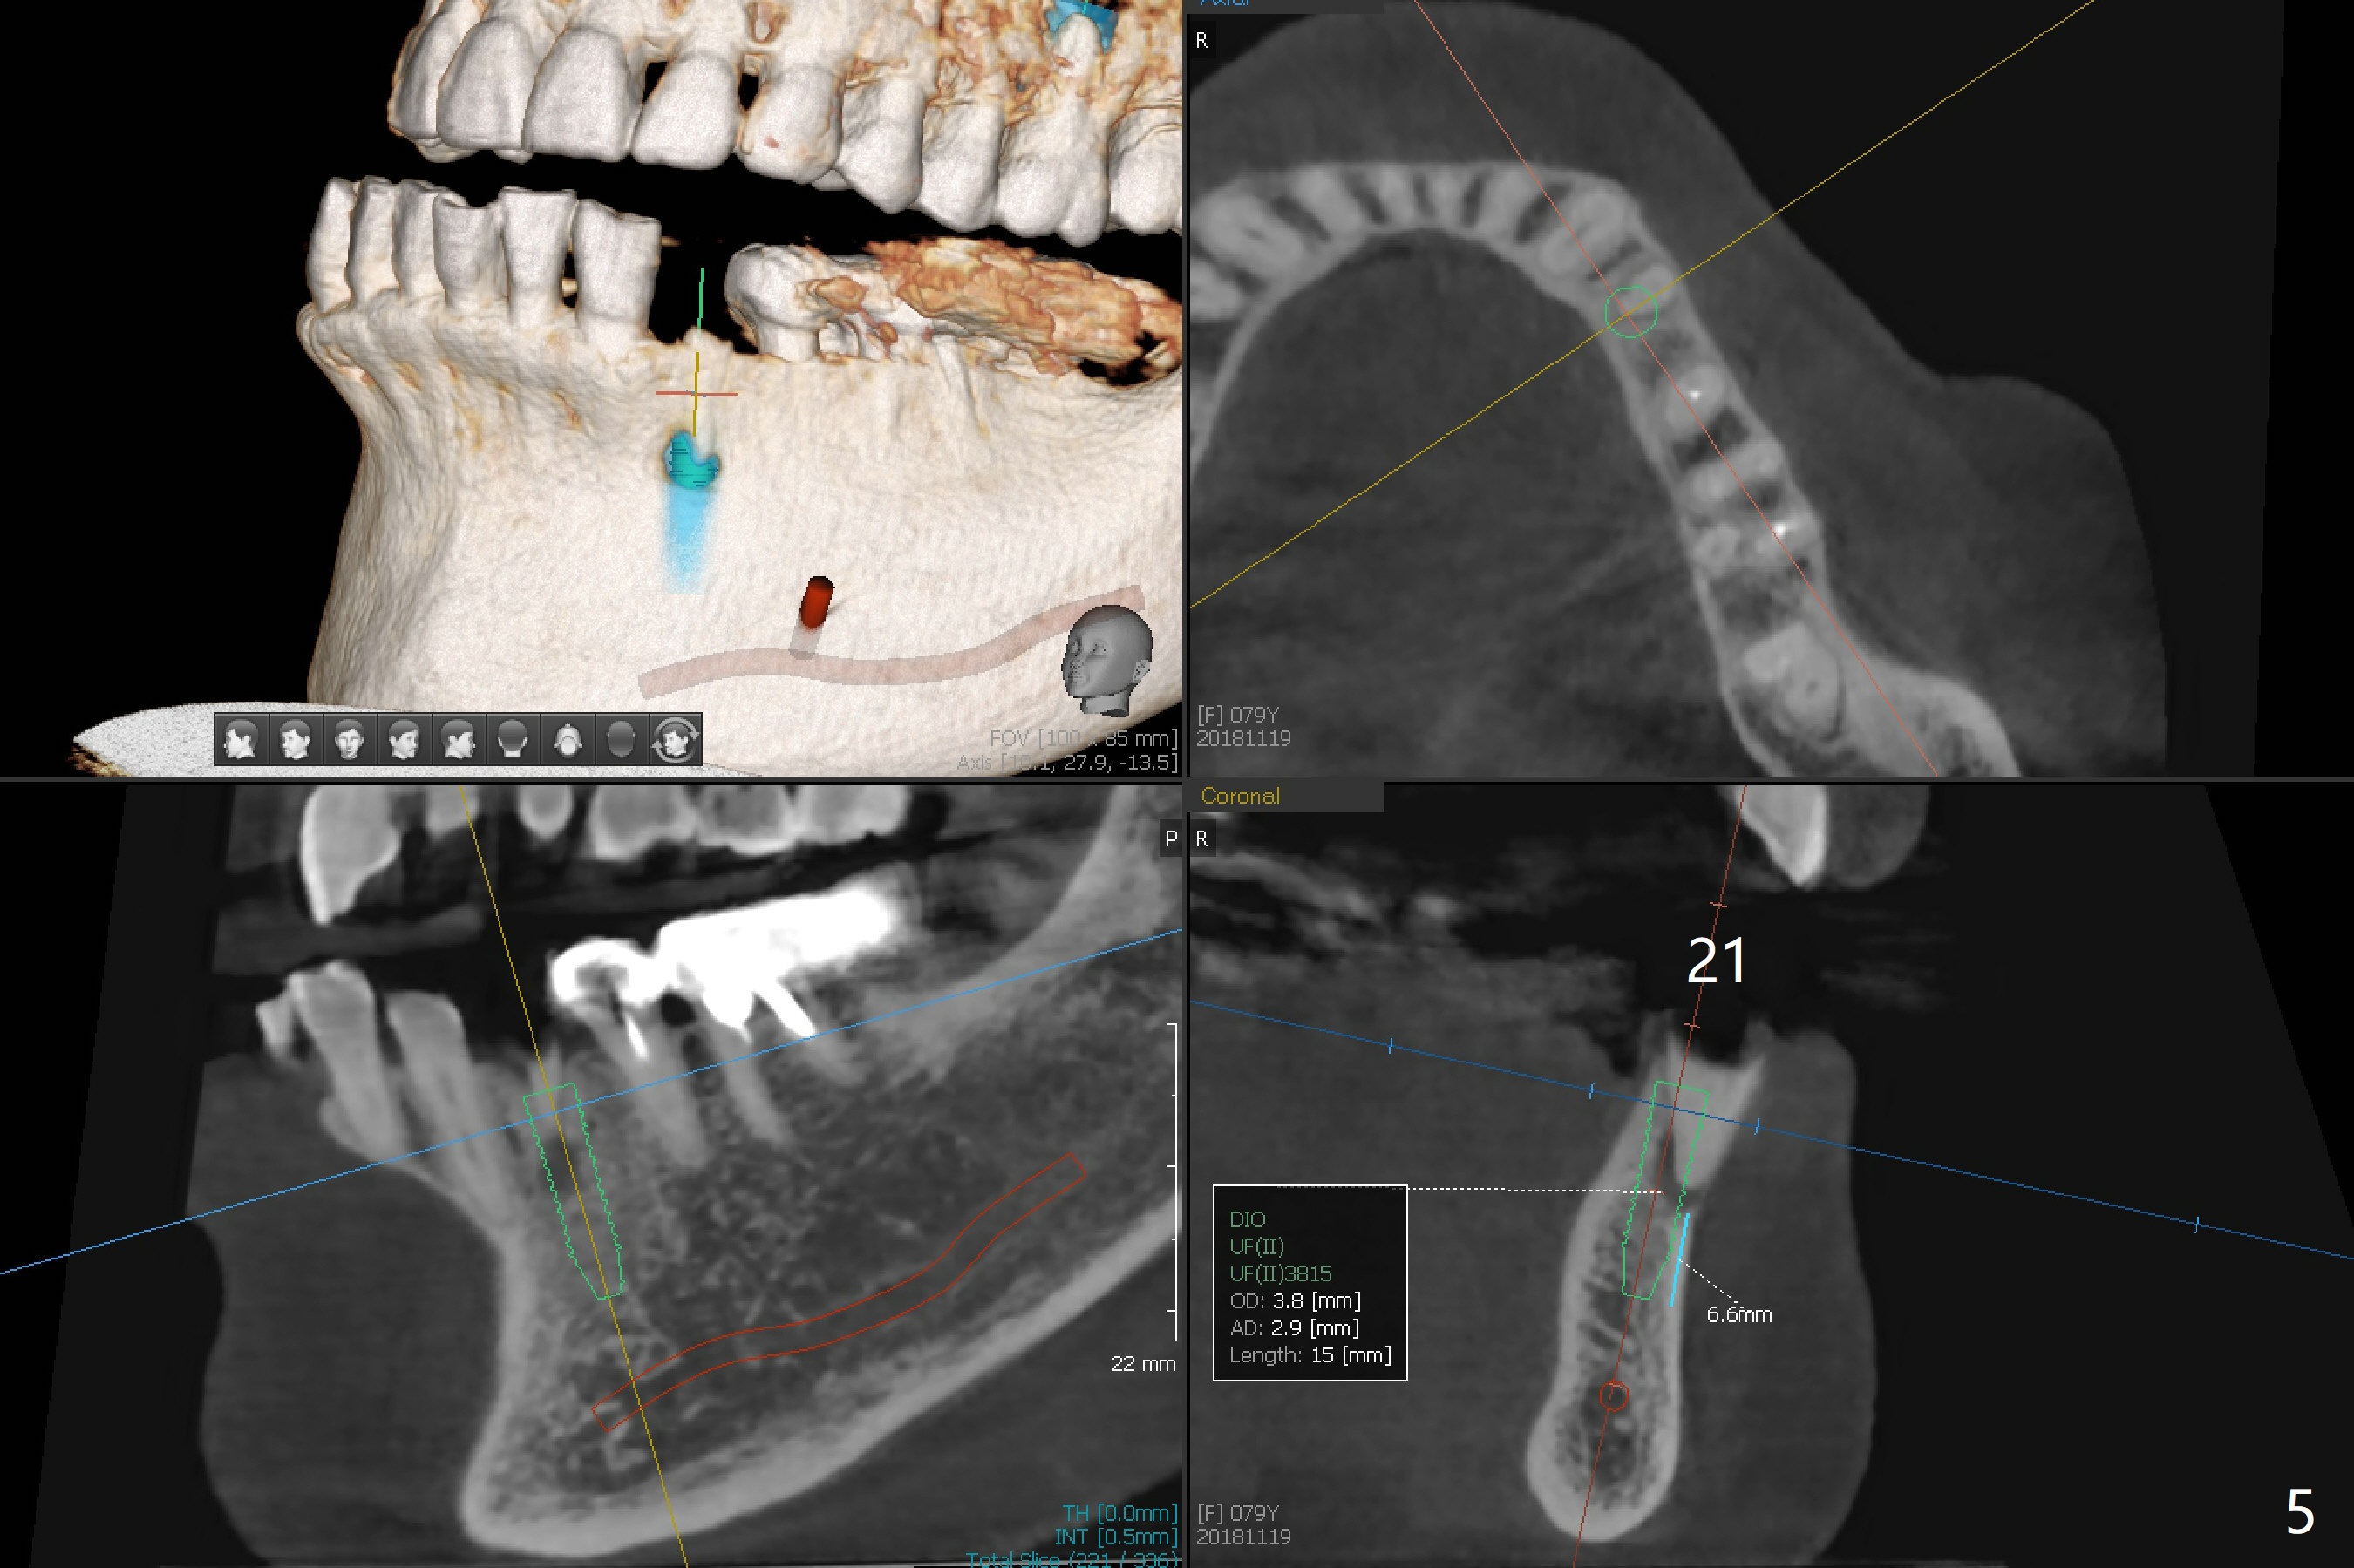

A 79-year-old woman has subgingival symptomatic caries at #14 and residual roots at #4 and 21 (Fig.1). Because of bilateral thick sinus membrane (Fig.2 *) with nasal obstruction, immediate implants at #14 and 4 will be placed without sinus lift (Fig.3,4). To obtain primary stability, a long implant will be placed at #21 (15 or 16 mm), while a narrower implant (3 mm 1-piece, Fig.6)) is safer than 3.8 mm one (2-piece, Fig.5) in term of preventing periimplantitis (buccal thread exposure). Impression has been taken for guide at #14.